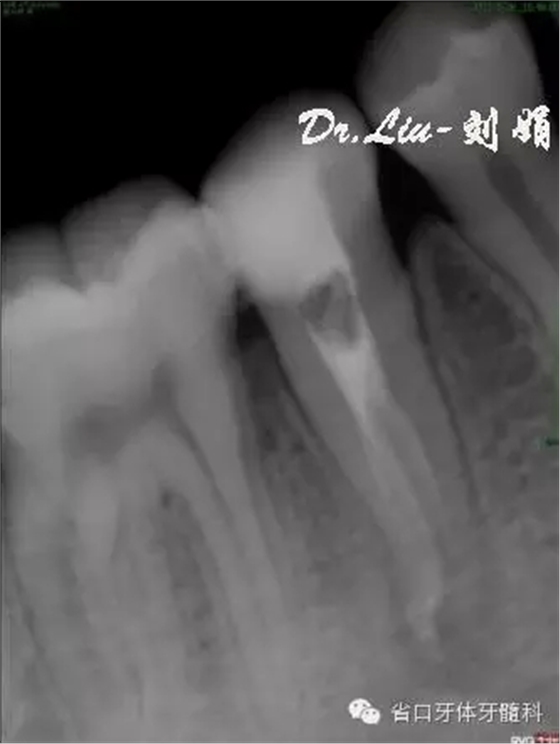

45橡皮障隔離下去封藥,清理根管,沖洗,紙尖干燥根管,拍攝試主尖片,顯微鏡下行熱牙膠根管充填,X線片顯示恰填。

圖9:試主尖

圖10:根充后X線片